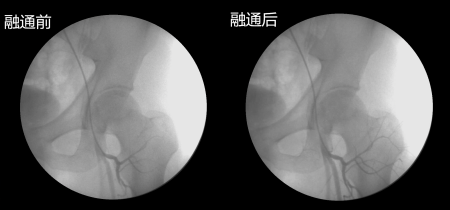

股骨头缺血性坏死之所以会坏死,首先是各种原因(激素,酗酒,外伤)等造成血液粘稠、以及形成大量的脂肪颗粒和血栓等,然后随着血液流淌,这些杂质不断沉积最终堵塞了股骨头的供血血管。 股骨头血管出现堵塞,失去了血液供应,骨细胞坏死 股骨头血供跟其他骨头不一样,它只有三根细小的血管供应,如果血管堵塞了,骨细胞没有得到营养的供应,骨细胞就会慢慢“饿”死,所以说只要疏通了这三根血管,同时建立起侧支循环,就解决了股骨头缺血性坏死的病根难题。而“可视血堵融通术结合血液净化”综合治疗诊疗体系正好可以打通血运,同时在血液和药物的作用下,还会促进周围毛细血管的再生,建立起骨质上所有的血液循环。比起手术治疗的带血管移植更具有科学性,带血管移植存活率较低,且那三根血管没有疏通,也很难长时间维持股骨头的血液供应。 广州强直葆髋医院史东主任表示:“可视血堵融通术结合血液净化”综合治疗诊疗体系治疗股骨头缺血性坏死,避免了传统药物治疗无效和手术置换伤害大问题。它是在360度可视的情况下,通过股动脉穿刺插管至旋骨内、外侧动脉及闭孔动脉,直接将溶栓药物以及扩血管药物在介入治疗系统(DFA)监视引导下注入股骨头供血动脉,使血管内形成的脂肪栓及小血栓溶解,骨内微小血管再通。使局部血管扩张,微循环缺血改善,疏通髋关节附近的微血管,增加侧支循环和改善股骨头营养。使坏死的骨质逐渐被吸收,或骨细胞增生,新骨形成,修复股骨头。 视频详解“可视血堵融通术结合血液净化”综合治疗治疗过程 这也是目前打通股骨头血脉的科学诊疗体系之一,特别是辅助先进的可视血循仪和冲击波等,使设备水平又上了一个新台阶。 患者姓名:朱先生 患者及诊断情况:朱先生长期饮酒造成双侧股骨头缺血性坏死,一年前开始疼痛,经过CT检查为双侧股骨头缺血性坏死,已经达到了二期,髋部疼痛剧烈。 初步诊断:酒精性双侧股骨头缺血性坏死二期 1、治疗方案:“可视血堵融通术结合血液净化”综合治疗+后期修复 2、病程记录:治疗后的第二天,患者一般情况可,诉疼痛减轻,未诉其它特殊不适。经过三天的病情观察,患者病情已经得到了控制,并且症状明显改善,继续观察病情。一周后,检查结果显示股骨头血液循环正常,骨细胞密度开始出现微变化,一切恢复都比较正常,患者出院,患处无异常。 3、出院医嘱:卧床休息,注意饮食;遵医嘱用药,医院将进行回访。恢复状况:2016年4月患者入院复查,疼痛消失,肌肉萎缩消失,可以自由走路,随访至今未现复发。 融通前后照片: 选择一所专业的好医院,一个科学规范的方案,可让患者健康一生 引发股骨头缺血性坏死的原因有很多种,但归根结底只有一种原因,那就是股骨头的"血管堵塞"引起的血供中断,造成骨细胞及骨髓成分死亡,继而导致股骨头结构改变、股骨头塌陷、关节功能障碍的疾病。在可视血循分析仪的辅助下将堵塞的血管通开。因此,诊断、治疗、复查股骨头缺血性坏死一定要前往设备报销的专业医院,切勿盲目选择、误入歧途。也在此提醒广大病友就医看病一定要认准医院和技术,不能听信一些广告就盲目就医,给自身带来伤害!